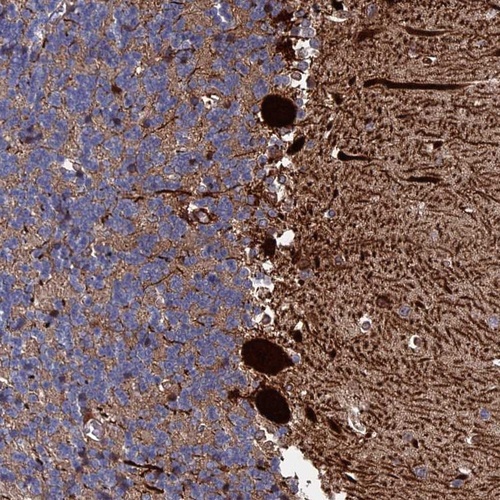

Immunohistochemical staining of human cerebellum shows strong cytoplasmic positivity in Purkinje cells.